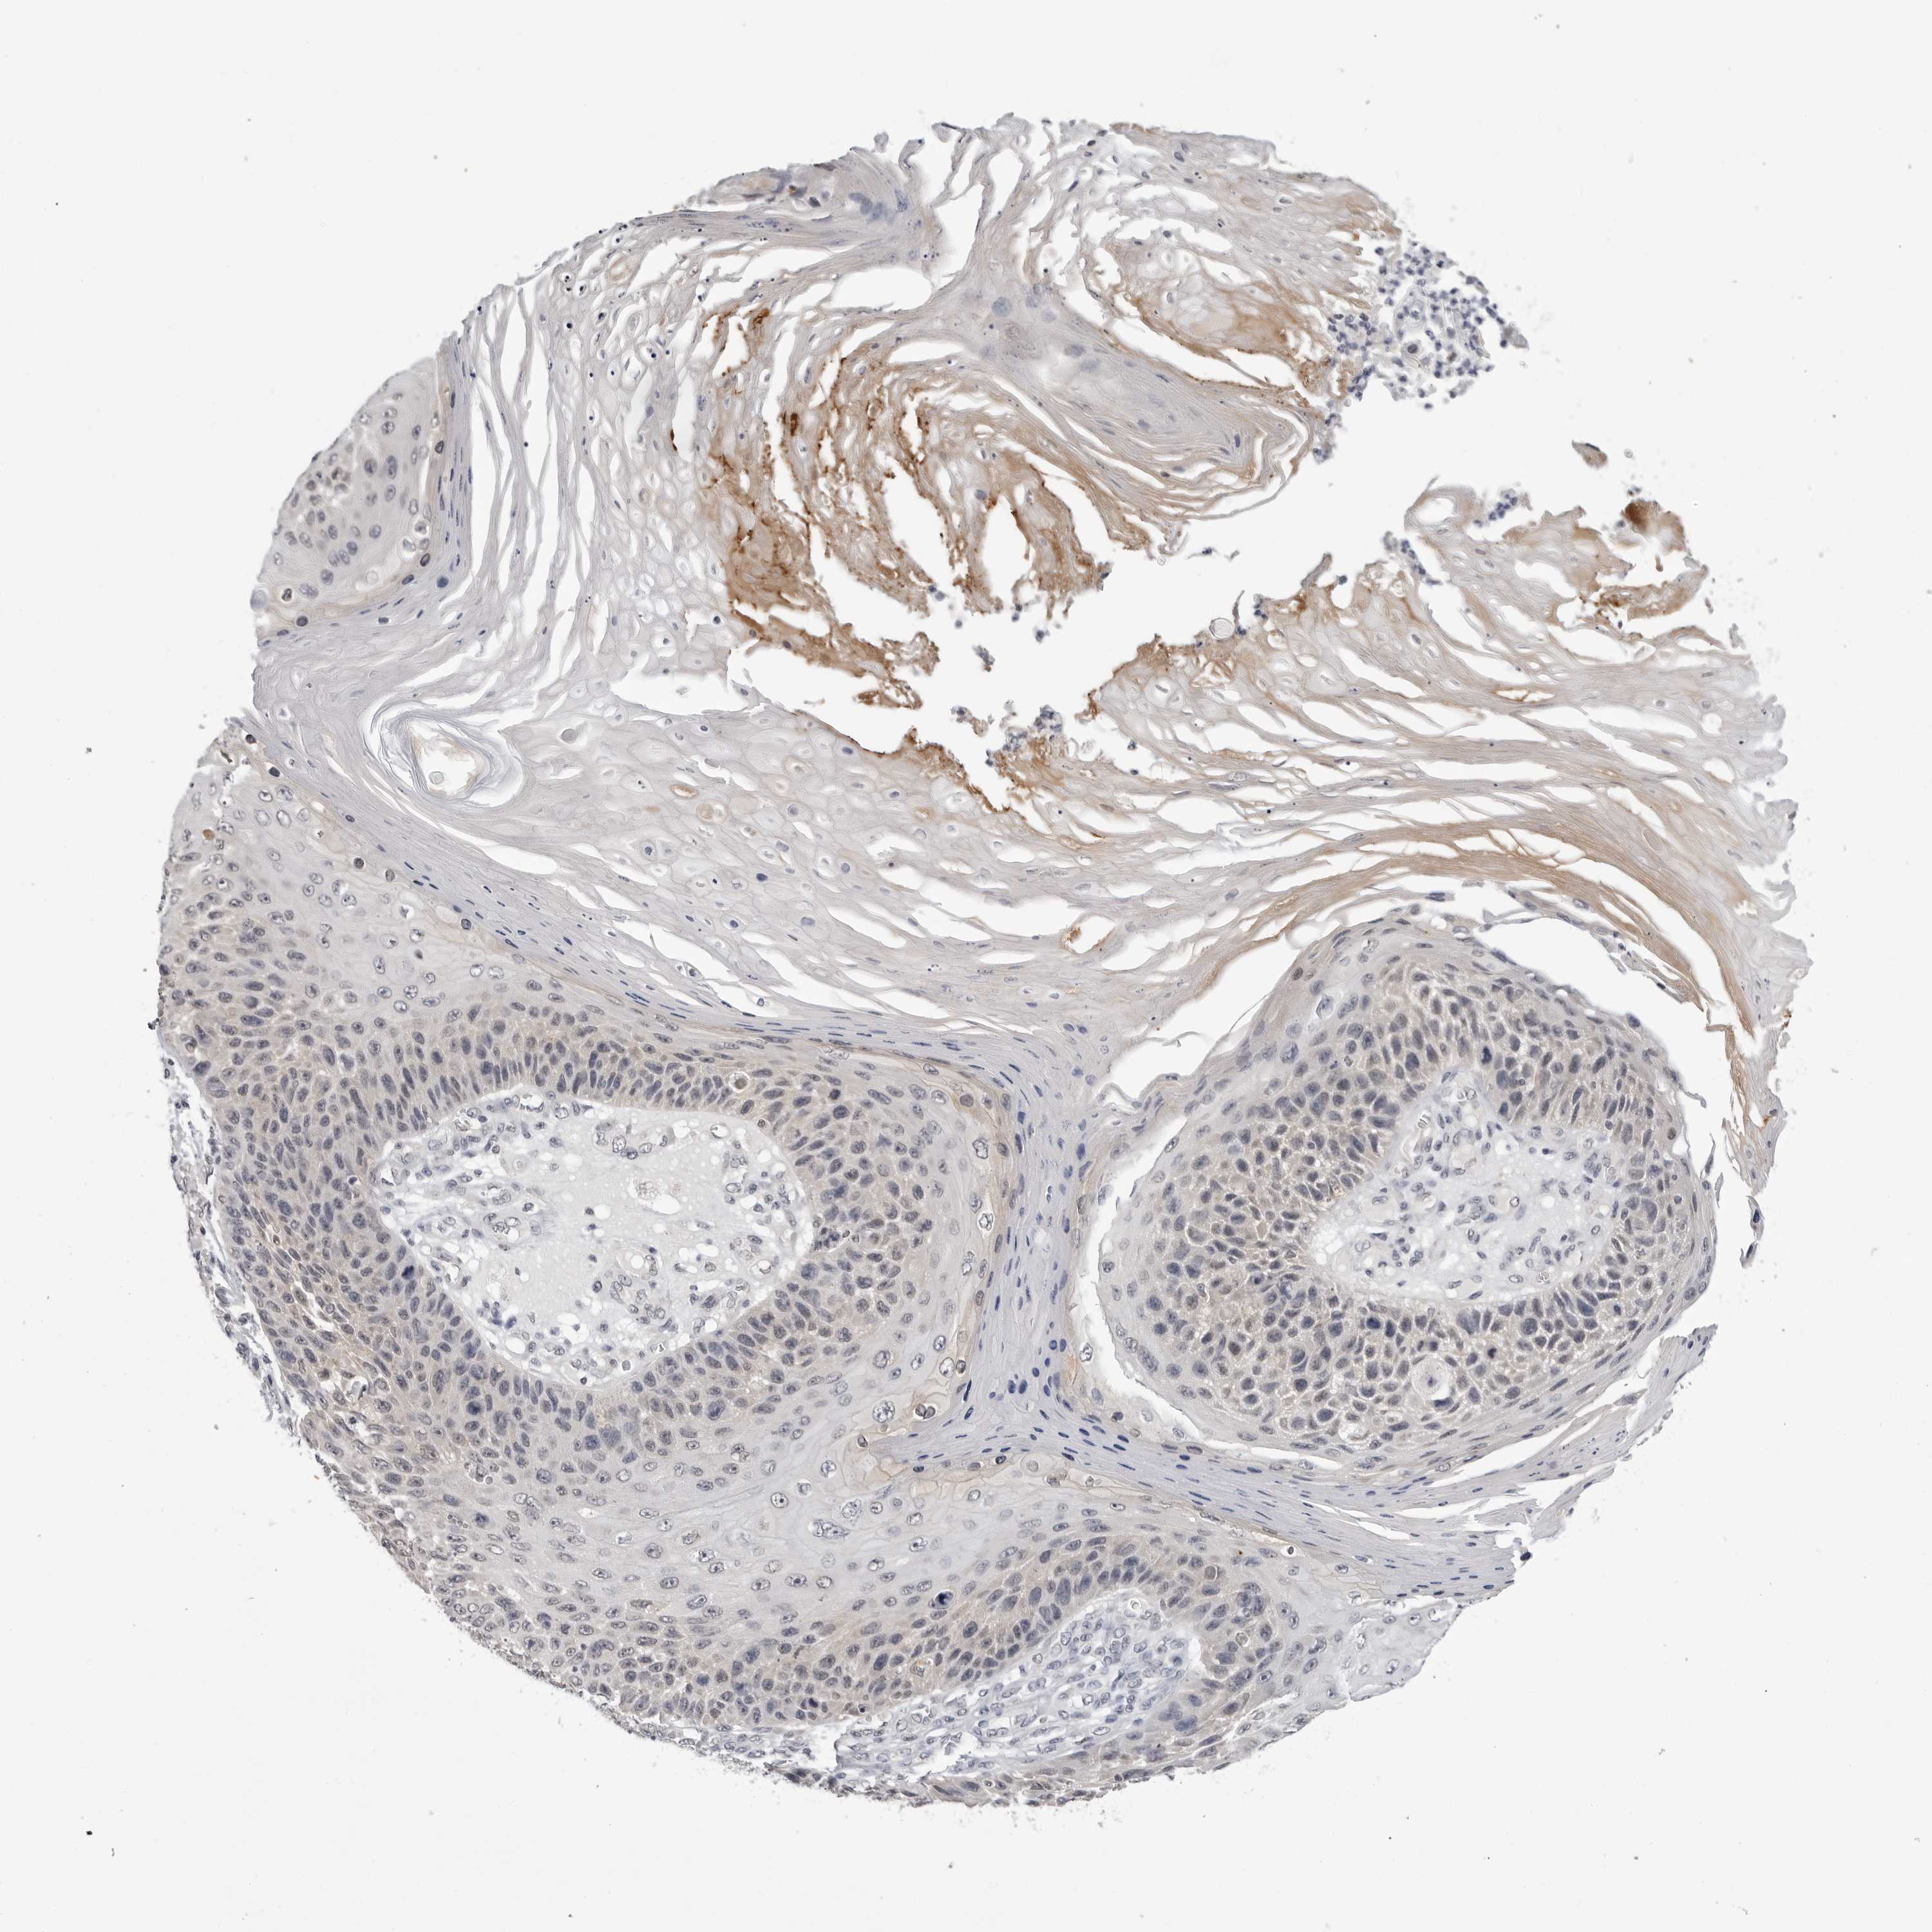

Basal cell and squamous cell cancer

SKIN CANCER - Protein expressioni

A mouse-over function shows sample information and annotation data. Click on an image to view it in a full screen mode. Samples can be filtered based on level of antibody staining by selecting one or several of the following categories: high, medium, low and not detected. The assay and annotation is described here.

Each image is clickable and will lead to virtual microscopy that enables deeper exploration of all samples and also displays staining intensity scores, fraction scores and subcellular localization as well as patient and tissue information for each sample.

Antibody HPA007666

Basal cell carcinoma